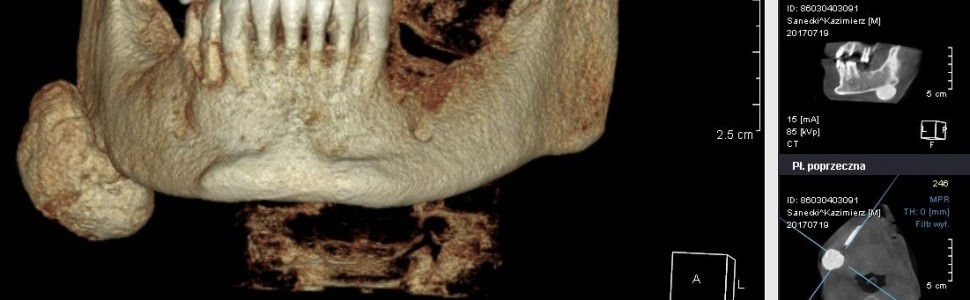

Kostniaki to łagodne guzy złożone z dojrzałej kości zbitej i gąbczastej. Dzielą się na obwodowe, centralne i pozaszkieletowe. Kostniaki obwodowe biorą swój początek z okostnej i wzrastają na powierzchni kości, centralne rozwijają się wewnątrz kości ze szpiku kostnego, a pozaszkieletowe zwykle obserwuje się wewnątrz mięśni. Kostniaki wykrywa się najczęściej w kościach twarzy i czaszki. Obecność kostniaków mnogich może być związana z zespołem Gardnera. Zmiany te są przeważnie bezbolesne, a wznowy po ich usunięciu występują niezwykle rzadko. Autorzy pracy prezentują przypadek 31-letniego pacjenta leczonego w Zakładzie Chirurgii Stomatologicznej z powodu kostniaka obwodowego, zlokalizowanego w pobliżu kąta żuchwy strony prawej.

Osteoma is a benign tumour composed of compact bone and cancellous bone. They are divided into peripheral, central and extra-skeletal. Peripheral osteoma originates from the periosteum and grows on the surface of the bone. Central osteoma develops in an intraosseous manner out of bone marrow. Whereas, extra-skeletal osteomas are often defined as intramuscular. Osteoma occurs most frequently in facial and skull bones. The incidence of multiple osteomas may be connected with Gardner’s syndrome. The lesions are usually painless and post-removal recurrences are extremely rare. The authors of the paper present the case of a 31-year-old patient, treated in the Department of Oral Surgery, suffering from peripheral osteoma located near the right mandibular angle.